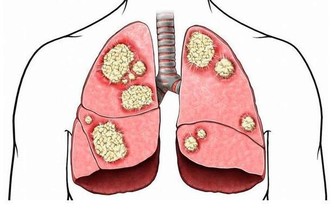

6、清除肺內毒素

人們每天除了會呼吸氧氣之外,還會吸過多的灰塵及細菌進入人的肺部,長期之後肺部會有諸多的毒素,毒素不但危害人體的健康,而且還會加速衰老,這時清除肺毒是有必要的。

每天早上或者晚上到環境較好的地方進行深呼吸,這樣可以使大量的新鮮空氣進入肺部,清除血液內毒素及自由基。從而達到清除肺部毒素的作用,延緩人體衰老。